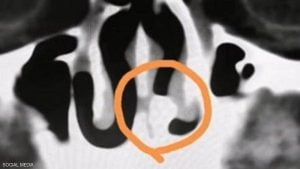

ووفقاً لما نشرته “سكاي نيوز عربية”، فإنه في أثناء الفحص بالأشعة السينية، لاحظ الأطباء وجود جسم ذي كثافة عالية في الجزء الخلفي من تجويف الأنف.. وقال أحد الأطباء: “لقد بدا الأمر وكأنها سن”.

وتبين لاحقا أن السن دخلت إلى الأنف، دون أن يشعر تشانغ، وأخذت في النمو هناك، في حالة نادرة للغاية يطلق عليها الأطباء “الأسنان المتحجرة داخل الأنف”.

ويقول خبراء، إنه تم تسجيل العثور على 23 حالة مسجلة فقط بين عامي 1959 و2008.

وأزال الأطباء السن التي يبلغ طولها نحو سنتيمتر واحد (0.4 بوصة)، من أنف تشانغ، بعد عملية جراحية مدتها 30 دقيقة.